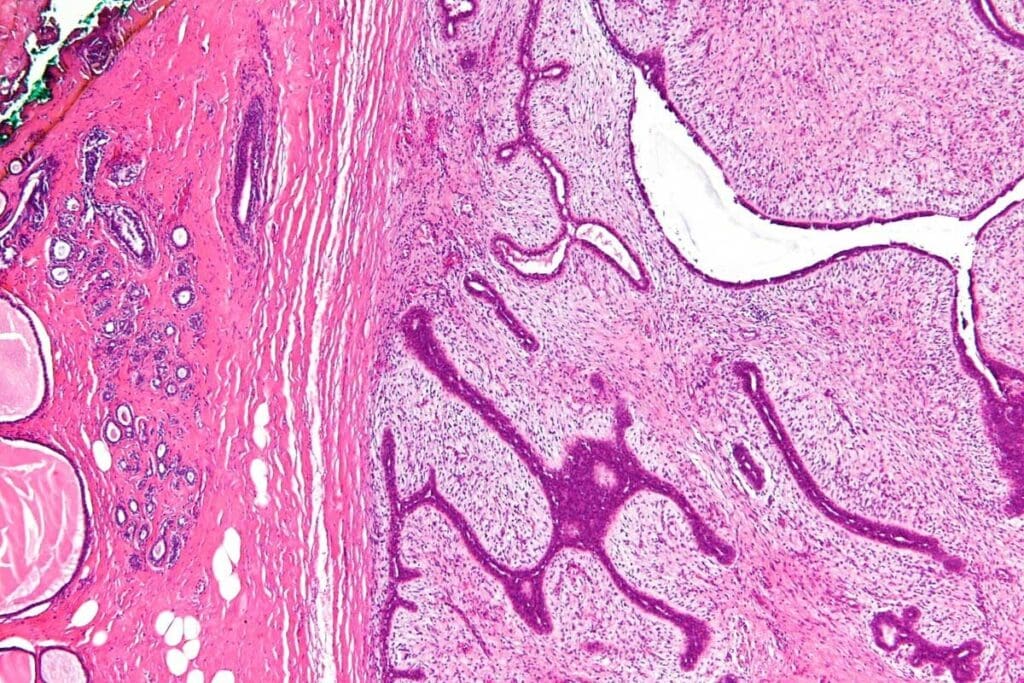

Muscle tissue tumors include both benign growths and malignant sarcomas. They can come from skeletal or smooth muscle cells. Knowing about these tumors is key to diagnosis and treatment.

Definition and Classification of Muscle Tissue Tumors

Muscle tissue tumors start from muscle cells. They are divided into benign and malignant types. Benign tumors, like leiomyoma, are not cancerous and don’t spread.

Malignant tumors, such as rhabdomyosarcoma, are cancerous and can spread. The type of muscle cell a tumor comes from helps classify it. This is important for choosing the right treatment.

Types of Muscle Tissue Tumors

Muscle tissue tumors include both benign growths and malignant sarcomas. They can happen in skeletal and smooth muscle. This variety makes treatment plans different for each case.

Leiomyoma: Benign Smooth Muscle Tumors

Leiomyoma, or uterine fibroids, are non-cancerous tumors of smooth muscle. They can grow in the uterus, stomach, and skin. Most leiomyomas don’t cause symptoms, but big ones can lead to problems.

Leiomyosarcoma: Malignant Smooth Muscle Tumors

Leiomyosarcoma is a rare, aggressive cancer of smooth muscle. It can show up anywhere in the body, like the uterus or soft tissues. It’s known for spreading quickly and needing strong treatment. Doctors usually use surgery, chemo, and radiation to fight it.